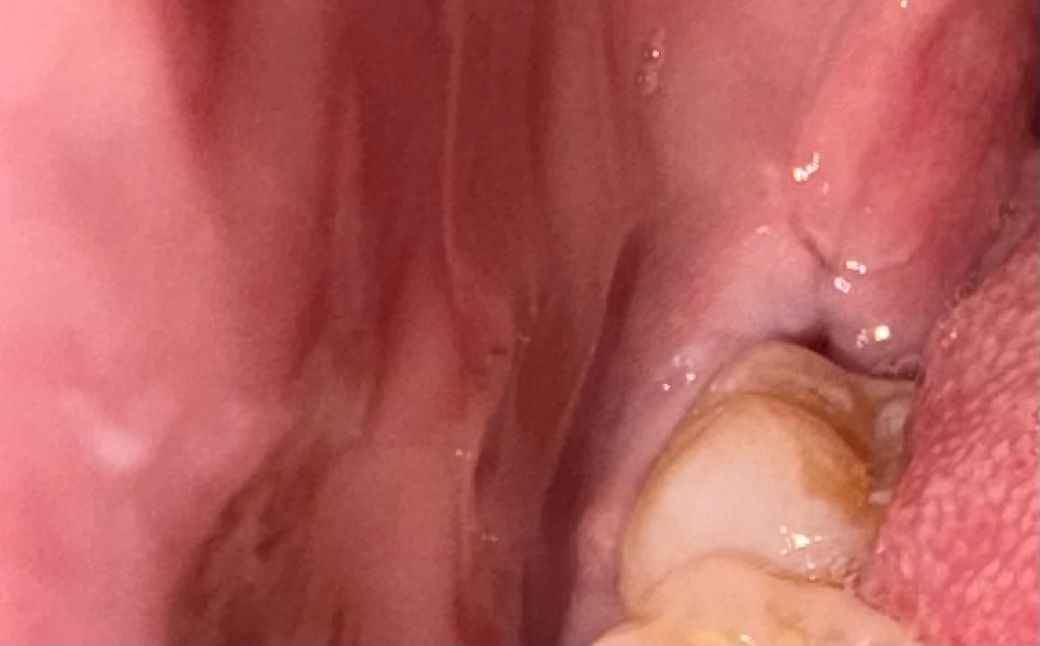

사랑니 실밥 제거 한 후 검은색 충치인가요????

어제 사랑니 뽑은지 일주일 지나서 실밥제거 했는데요

검은색이 보여서요 이게 충치인가요 그냥 구멍인가요?

사진으로 보이는 검은색은 사랑니를 발치하고 생긴 구멍으로 보입니다.

이런 구멍은 시간이 지나면서 자연스럽게 메꿔지기 때문에 발치를 한부위를 자극하지 않는것이 좋습니다.

그냥 구멍이고 1달정도면 아물면서 닫힙니다 음식 드셔도 되는데 음식물 안끼어있게 잘 빼주셔야 합니다